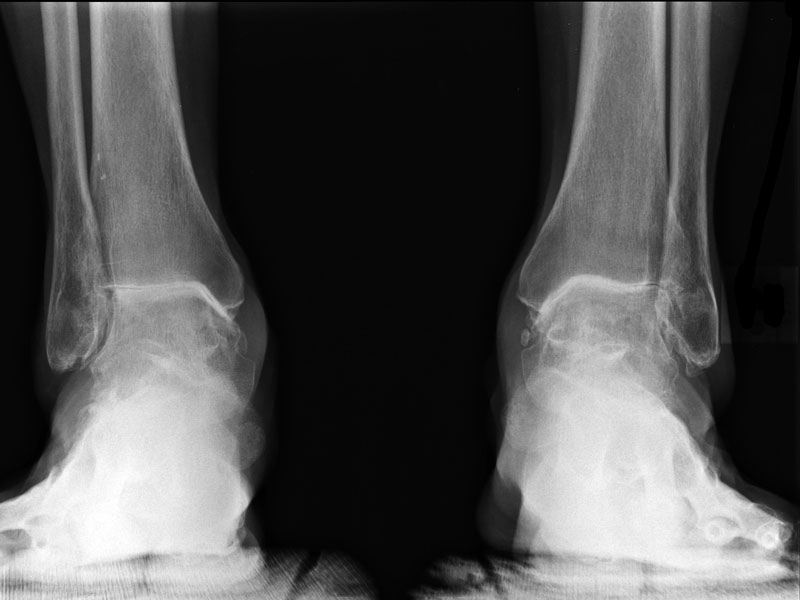

Основаниями для выставления первичного диагноза становятся внешний осмотр пациента, его жалобы, данные анализа. Врач проводит ряд функциональных тестов для определения мышечной силы, чувствительности, объема движений в стопе. Для подтверждения диагноза назначаются инструментальные исследования:

- рентгенография для оценки деструкции костных структур, обнаружения сформировавшихся наростов (остеофитов);

- МРТ, КТ для детального изучения состояния хрящей, кровеносных сосудов, мышц, связочно-сухожильного аппарата;